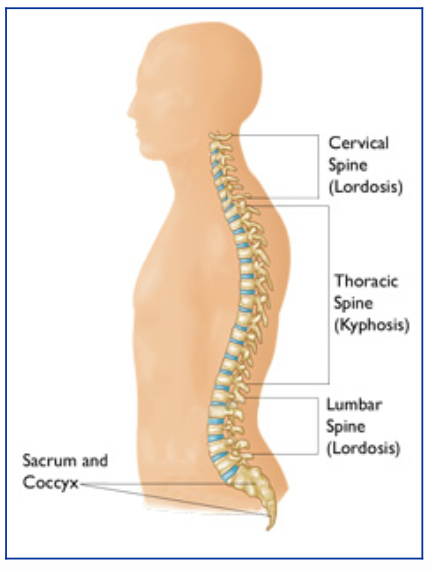

Измерение кифоза грудного отдела: Рентгеновские снимки